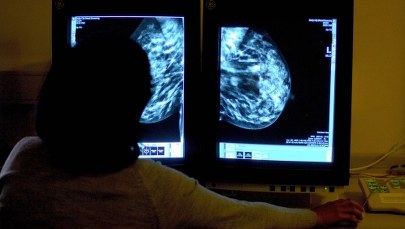

Wciąż wśród mężczyzn najczęściej występuje rak płuca i to on jest największym zabójcą. Odnotowujemy najwięcej zgonów z powodu tego nowotworu także wśród kobiet, mimo że wśród nich najczęściej występuje rak piersi. To jest niepokojące - mówi profesor Jacek Fijuth. Zgodnie z trendami cywilizacyjnymi i tym, że społeczeństwo starzeje się, zwiększa się liczba nowotworów, które występują zwykle w późniejszym wieku, które są typowe dla społeczeństwa bardziej dostatniego. U mężczyzn to rak gruczołu krokowego, u kobiet to rak trzonu macicy. Wciąż na wysokim poziomie jest liczba zachorowań na raka jajnika czy raka szyjki macicy, zwłaszcza w tych wyżej zaawansowanych stadiach - dodaje prezes Polskiego Towarzystwa Onkologicznego.